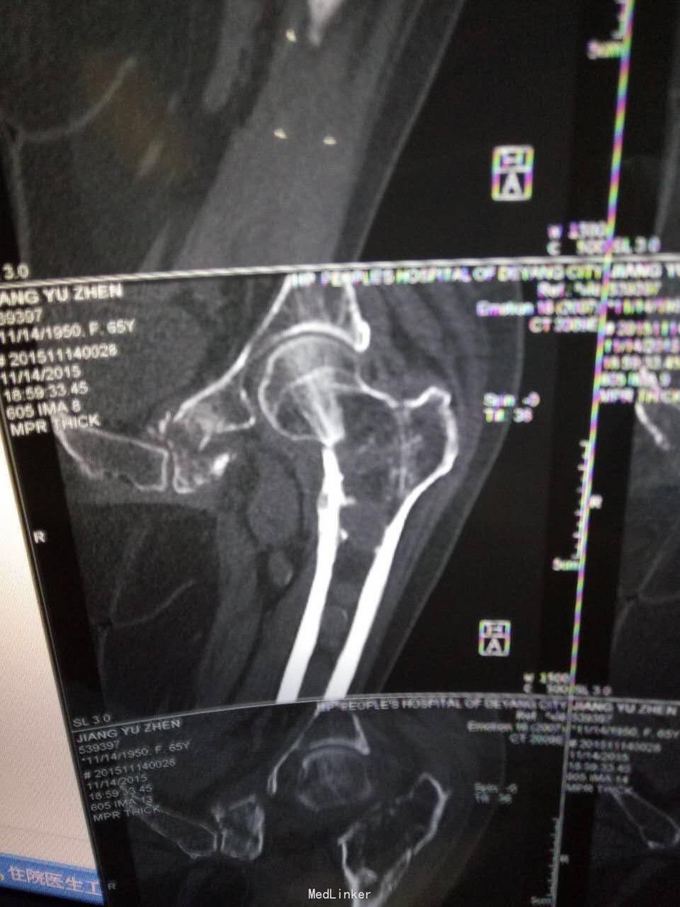

主诉:摔伤致左髋部疼痛及活动受限1小时; 病史:1小时前患者不慎摔伤,致左款疼痛,活动受限。无开放性伤口。患者半年前于华西诊断重度骨质疏松症,长期注射鲑降钙素,密固达一次。

查体,左下肢外旋畸形,髋部压痛,轴向叩击痛。 x片提示:左股骨颈、转子间骨折,左股骨耻骨上支,耻骨联合、下肢粉碎性骨折。

诊断:左股骨颈、转子间粉碎性骨折,左耻骨上支、耻骨联合、下支粉碎性骨折,重度骨质疏松症, 处理:患肢制动,牵引,注射鲑降钙素,科室讨论意见为行髋关节置换术,与换方沟通后,换方表示拒绝手术治疗,主动出院。